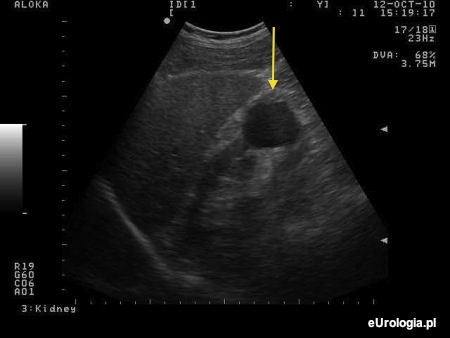

Domyślamy się, że określenia cysta używa Pan mając na myśli torbiel prostą nerki. Torbiel prosta jest cienkościenną przestrzenią wypełnioną płynem. Torbiel o takich rozmiarach i lokalizacji nie wymaga dodatkowej diagnostyki i leczenia. Więcej informacji znajdzie Pan w artykule: Torbiele proste nerek.

Fot. Torbiel prosta dolnego bieguna prawej nerki.